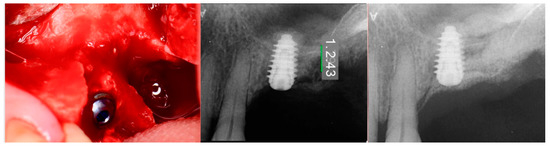

At 10 weeks post-extraction, the patient presented, and consent forms were reviewed and signed for grafting and implant treatment. Soft tissue had healed, closing the site with keratinized tissue (Figure 8, middle). A radiograph was obtained to check what available bone was present at both sites (Figure 8, right). Sufficient height was available to place an implant at the 1st molar site in conjunction with a crestal sinus augmentation, but insufficient height was present at the 2nd molar site which would require grafting to increase crestal height and later implant placement could be performed at that site.

Local anesthetic was administered, and a full thickness flap of the area was elevated. Utilizing a similar technique as outlined in case 1, the 1st molar site underwent a crestal lift and a 4.5 × 8.5 mm Anyridge (Megagen, Busan, Republic of Korea) implant was placed (Figure 9). The defect present at the 2nd molar site, resulted in a crestal height of 1.5 mm, which was insufficient for implant stability if a simultaneous crestal sinus left was performed (Figure 9, middle). Thus, grafting would need to be performed to prepare the site for later implant placement. EthOss graft material was hydrated in the syringe as previously described and placed into the defect to increase crestal height following healing (Figure 9, right).

Figure 9.

Site was reentered at 10 weeks post-extraction and an implant was placed with a crestal sinus augmentation utilizing EthOss graft material at the 1st molar site and a large defect was present at the 2nd molar site (left), with a radiograph obtained to document the implant placement at the 1st molar and grafting of the defect (middle) and following crestal grafting of the 2nd molar site (right). Green line is the measurement of the height of the bone at that point between the crest and the sinus floor.

The patient returned at 10-weeks implant and graft placement and the soft tissue over the posterior quadrant was noted to be healed with no inflammation present (Figure 10 left). Following local anesthetic administration a full thickness flap was elevated and the previously grafted 2nd molar crestal area was filled with immature host bone (Figure 10 right). A radiograph was obtained, which noted a crestal height of 7.1 mm present (Figure 11 left). The 2nd molar site was prepared in a similar fashion as previously detailed, utilizing Densah burs to osseodensify the area and accomplish a crestal sinus augmentation and a 5 × 8.5 mm Anyridge implant was placed (Figure 11 middle and right). An impression of the 1st molar implant was obtained to initiate its restoration while the 2nd molar implant was integrating. A healing abutment was placed on the implant at the 1st molar and a cover screw on the 2nd molar implant and a radiograph obtained to document the clinical result to date (Figure 12).

Figure 11.

Radiograph demonstrating sufficient height of the ridge to allow primary stability of an implant placed at the 2nd molar with a crestal sinus augmentation at 10 weeks of graft healing (left), site preparation for the crestal sinus augmentation (middle) and implant placement into the site (right). Green line is the measurement of the height of the bone at that point between the crest and the sinus floor.